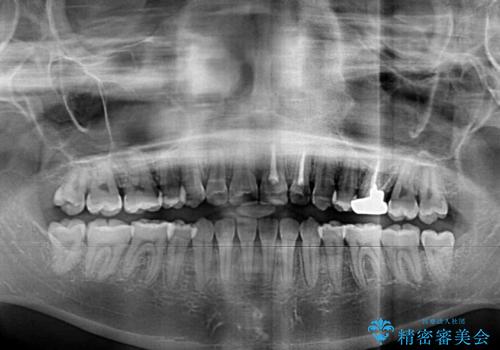

- 上の八重歯を気にして来院された患者様です。

受け口傾向にあるため、上顎前歯の叢生解消とともに下顎前歯を後方へ移動させることを目的とし、上下左右の第一小臼歯4歯を抜歯することとしました。

受け口傾向の方の下顎抜歯矯正では、下顎前歯の歯肉が退縮することがあります。前歯を移動させるときには、歯肉退縮が起こらないように工夫する必要があります。